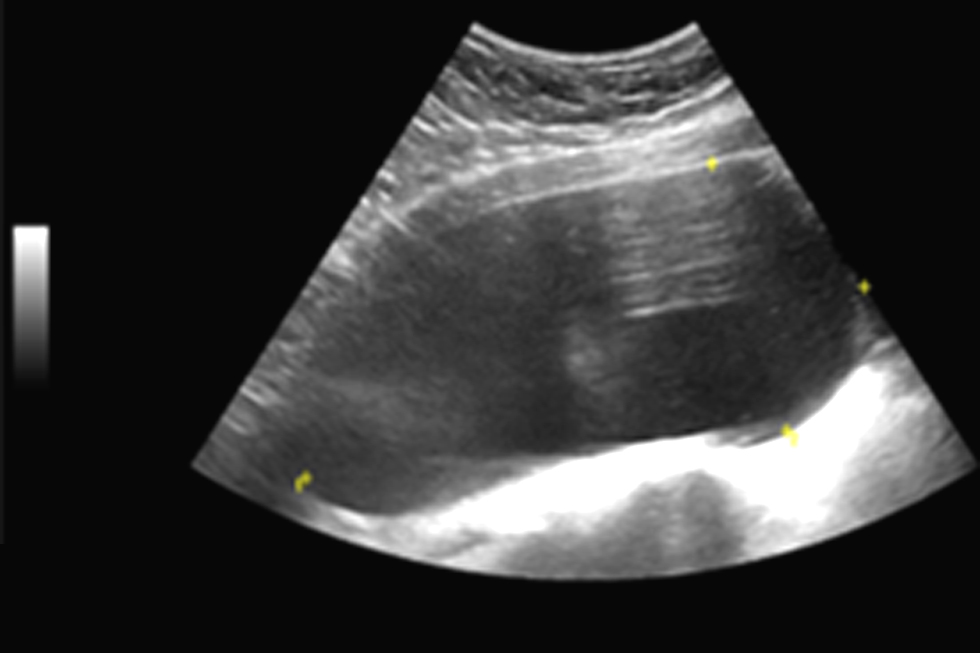

Figure 1 - Simple cyst originating from left ovary in abdominal ultrasound

One year after total thyroidectomy, the patient complained of hypogastric discomfort and low vesical compliance, with increasing levels of urinary creatinine. Her TSH levels had increased again to >100000 UI/mL. A simple left ovarian cyst with 174 x 80 mm compressing the bladder was identified in abdominal-pelvic ultrasound (fig. 1). Magnetic resonance confirmed the presence of an OC (175 x 140 x 100 mm) in the left ovary and the absence of loco-regional aggressiveness findings (fig. 2). She had normal levels of FSH and LH, non-elevated testosterone or oestradiol levels and normal serum levels of beta-hCG, alpha-fetoprotein and CA-125. The patient had no previous history of menstrual cycle irregularities and no OC had been identified in previous imagiological abdominal exams.